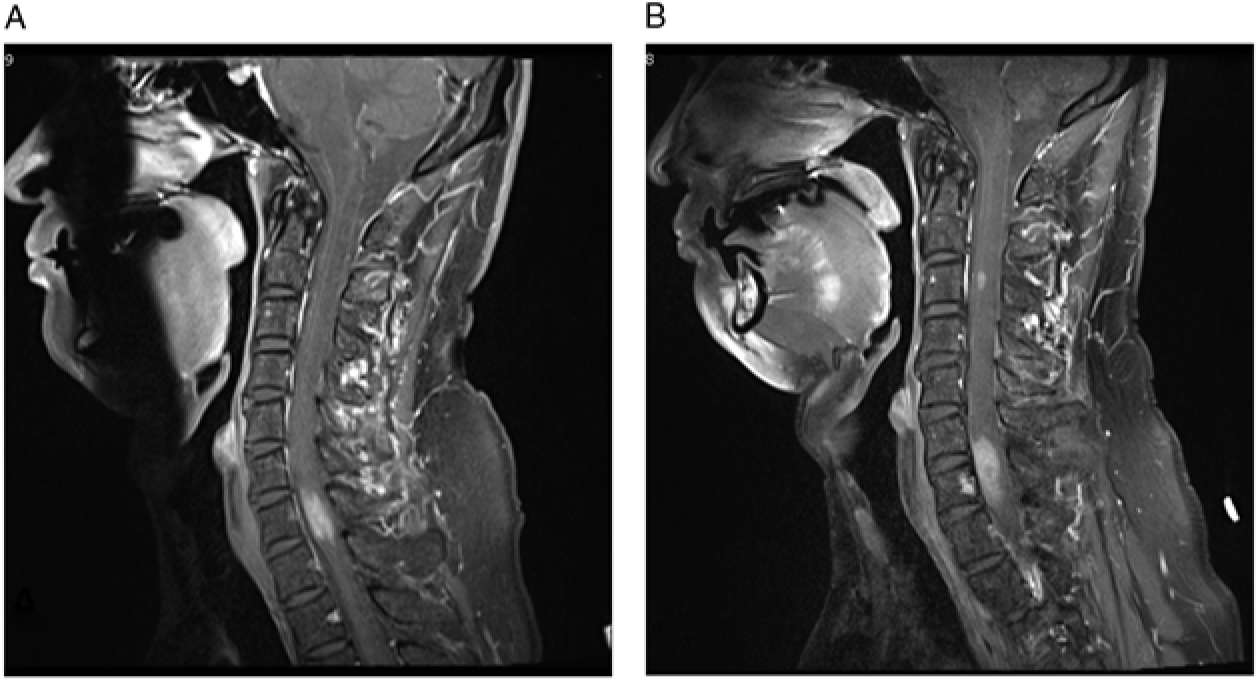

Magnetic resonance imaging (MRI) showed an expansile 2.5 cm enhancing lesion in the right cervical hemicord centered at C7 (Figure 1A). The radiographic features of germinoma are relatively nonspecific, usually hypointense on T1-weighted images and iso- or hyperintense on T2-weighted images.Reference Rosenblum, Nakazato and Matsutani1 They are often solid and more homogeneously contrast-enhancing on CT and MRI than other GCTs,Reference Rosenblum, Nakazato and Matsutani1 but the radiologic differential diagnosis remains broad. This includes neoplasm (glioma, hemangioblastoma, lymphoma, melanoma, GCT, metastatic carcinoma, and sarcoma) and non-neoplastic lesions comprising inflammatory (infectious causes such as tuberculosis and non-infectious causes such as sarcoidosis, demyelinating plaque, and progressive multifocal leukoencephalopathy) and other etiologies (e.g. vascular malformation).Reference Rosenblum, Nakazato and Matsutani1

Figure 1: (A–B) T1-weighted post-contrast images demonstrate the progression of cervical spine lesions over time. (A) MRI scan at first admission, demonstrating hyperintense lesion centered at C7. (B) MRI scan 11 months after initial presentation, demonstrating enlargement of the original lesion and a new lesion at C3 level.

Our patient’s MRI of brain, CT of chest, abdomen, and pelvis, and scrotal sonogram were normal at the time of presentation and 18 months later. MR angiography of the neck and intracranial vessels was normal. He did not respond to a trial of steroids, but his symptoms remained fairly stable. Serial MRIs revealed no change until 11 months after presentation at which time a new enhancing nodule (5 mm) appeared at the C3 level, along with slight progression of the original C7 lesion (Figure 1B). Around this time, the patient noted numbness involving his right thorax, but he declined biopsy for a further number of months.